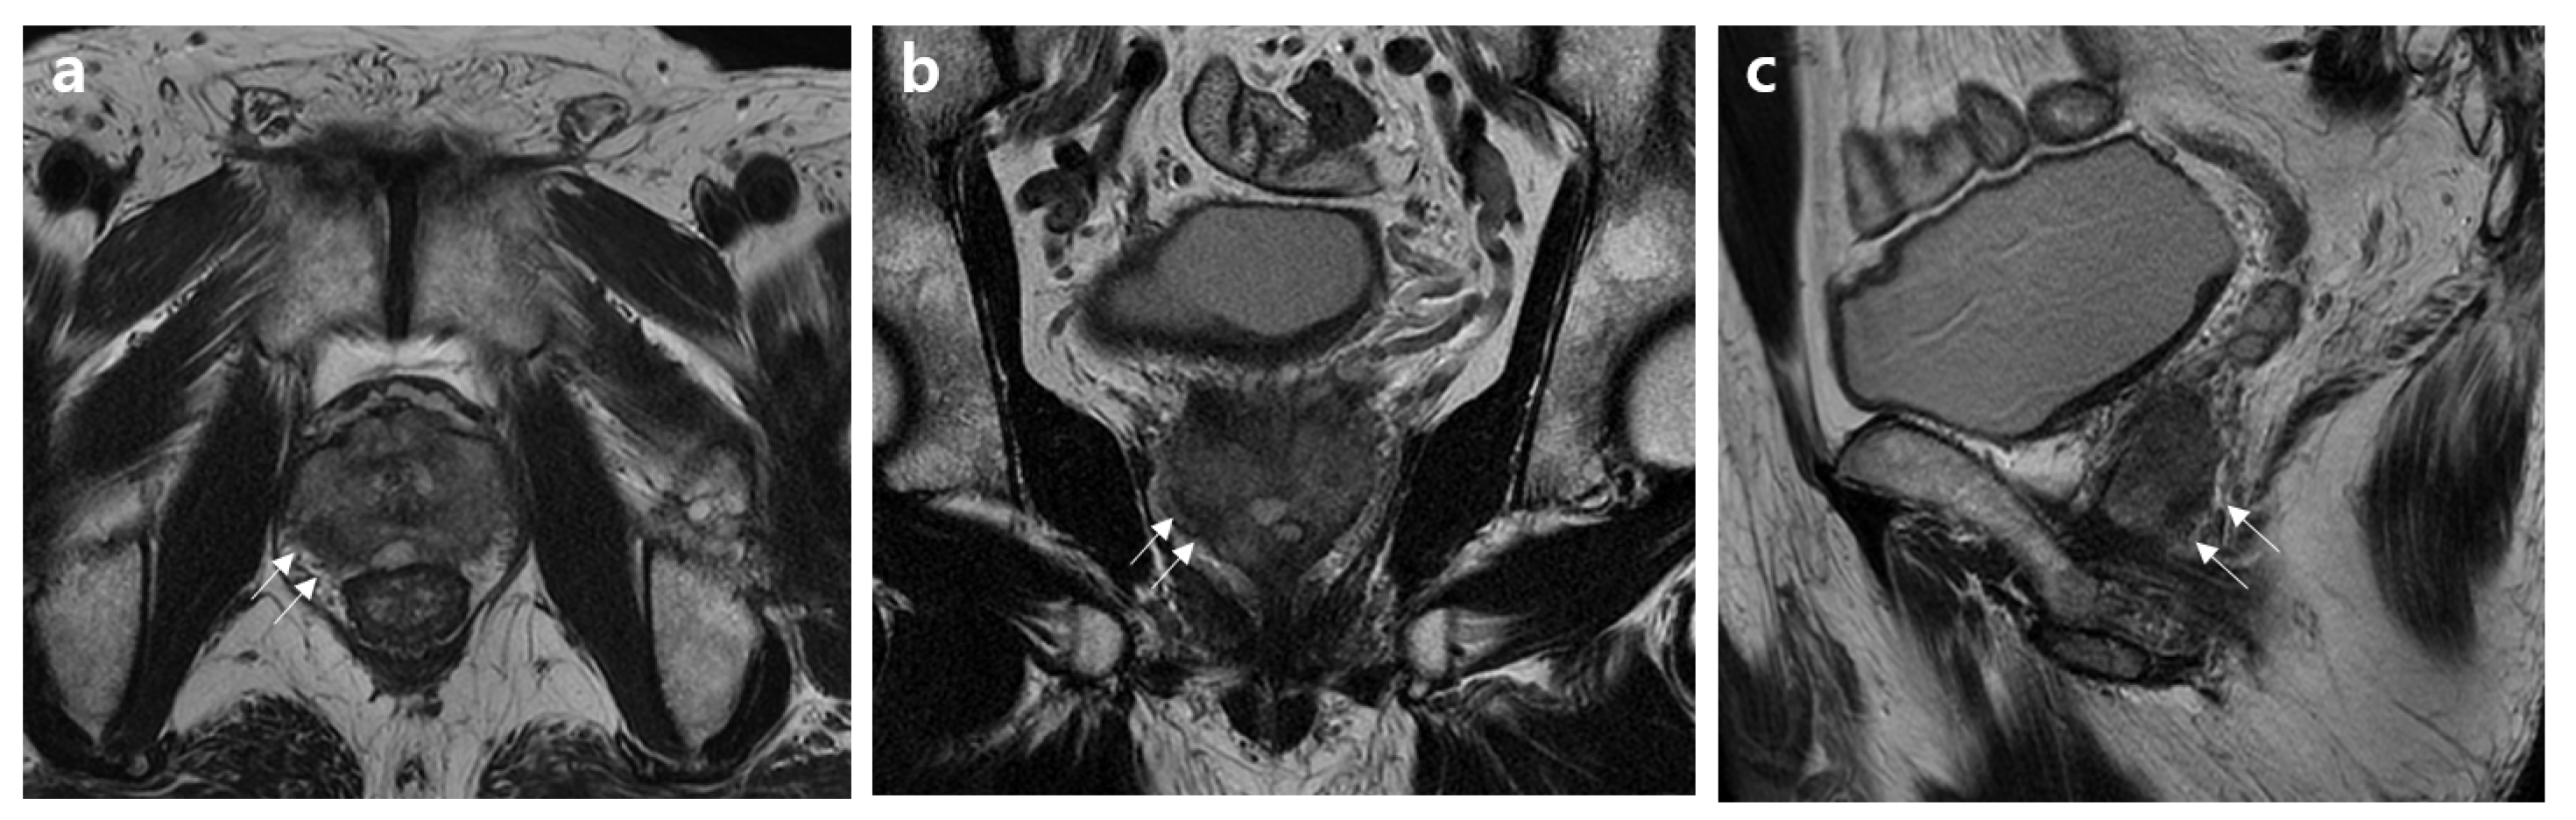

2.2. MRI Assessment